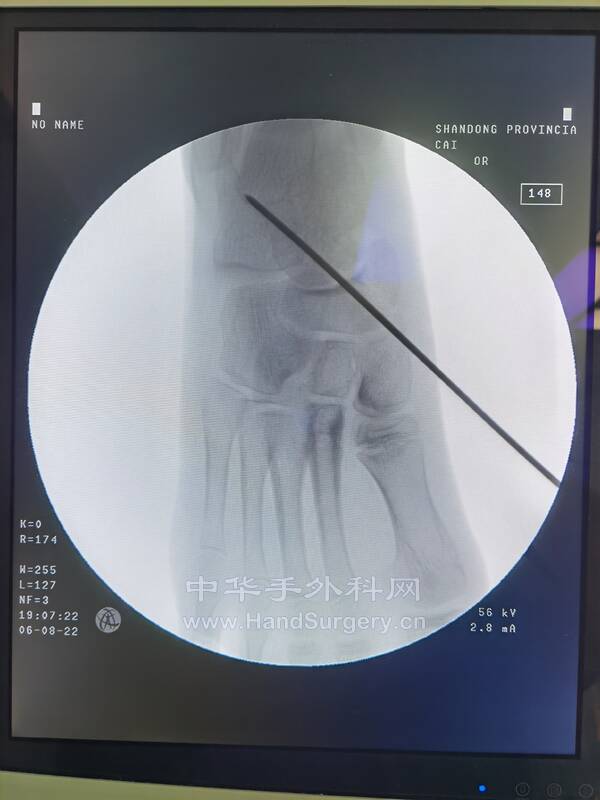

今日门诊女,38岁,距骨脱位,足下垂 诊断:术式:2022-6-29 15:30--19:50

1.跖筋膜松解

2.跟腱延长

3.胫前肌腱松解转位(固定在第三腓骨肌腱)

4.胫后肌腱和踇长伸肌腱松解

5.距下关节融合

6.环形外固定架固定

今日术后38天复查